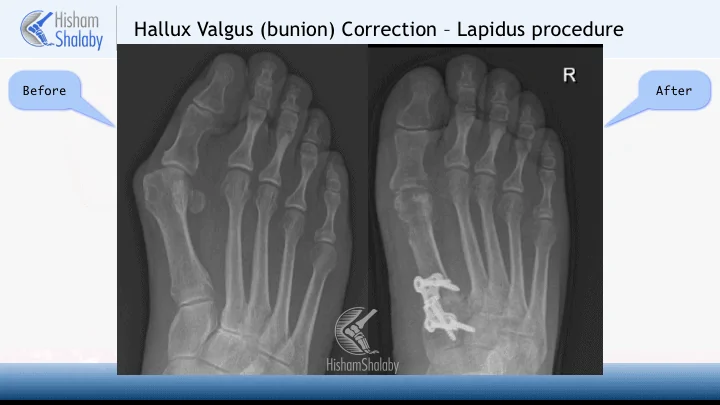

The operation involves two incisions. One is in the first web space to do a soft-tissue release of the structures that pull the toe to the deformed position. The second is a medial incision that is used to trim the bunion and to perform a break in the foot bone called “The Scarf osteotomy”. Another break in the toe itself called “The Akin osteotomy” is usually also performed.

These two breaks (or osteotomies) are used to set the toe straight. A medial soft-tissue tightening is also performed.